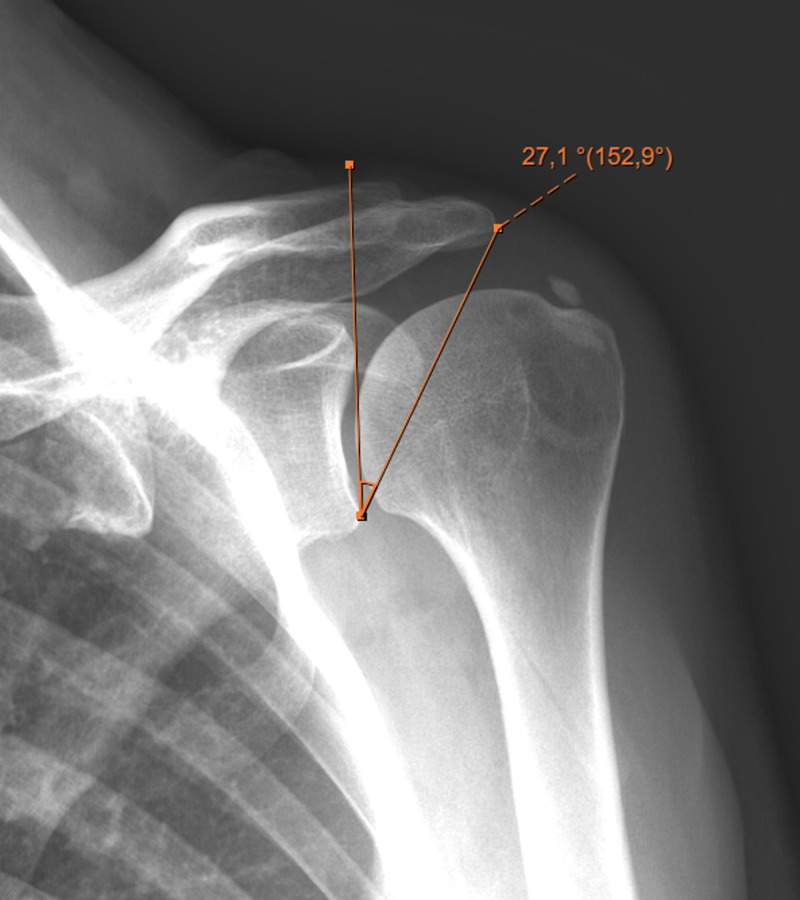

Methods: Ninety-two patients (33 male, 59 female; mean age: 47 ± 9.7) with calcific tendonitis were included in this retrospective study. Critical shoulder angle (CSA), slope angle, lateral acromial angle (LAA), acromion index (AI), acromial type according to Bigliani, and the morphology of the calcific deposits according to Gartner and Heyer were assessed on x-rays. The localization and volume of the calcific deposits were assessed using magnetic resonance imaging (MRI). Patients were divided into 2 groups: CSA < 33° (group 1) and CSA ≥ 33° (group 2).

Results: The median CSA was 33.5° (range=23°-51°), lateral acromial angle (LAA) was 83.6° (range=60°-106°), acromial index (AI) was 0.7 (range=0.4-0.9), and slope angle was 24.1° (range=3°-40°). Lateral acromial angle (P=.000) and AI (P=.000) were statistically different between the 2 groups. Critical shoulder angle was correlated with LAA (P=.000) and AI (P=.000); deposit volumes were correlated with slope angle (P=.001), Bigliani type of the acromion (P=.009), and deposit stage according to Gartner and Heyer (P=.004). There was a correlation between deposit localization and its volume; the size of the deposit increased anteriorly (P=.000).